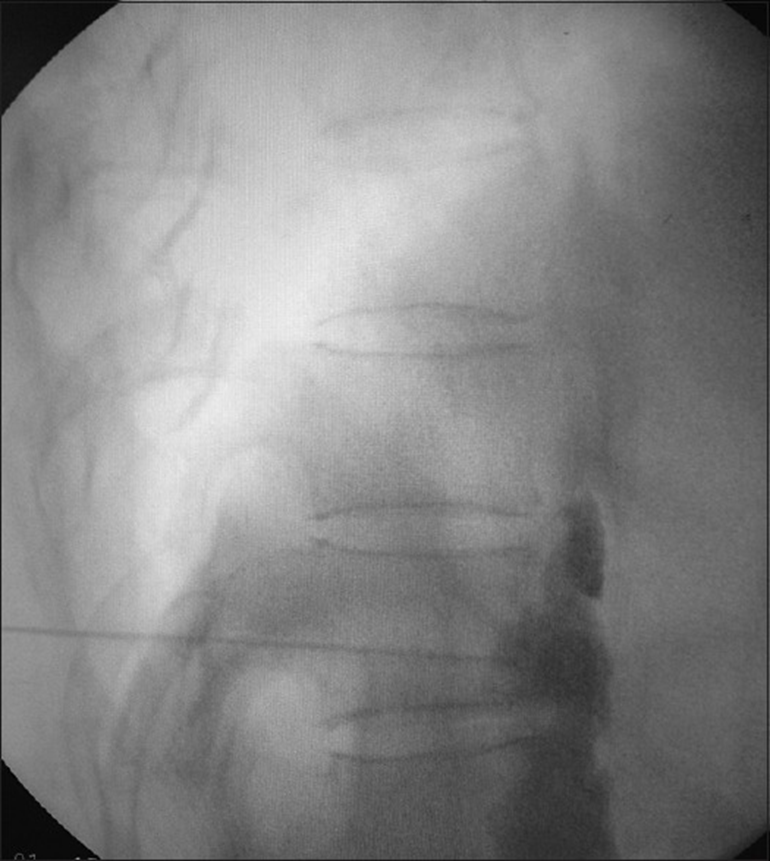

A small volume of contrast medium is injected to check dispersion along the anterolateral aspect of the vertebral body.

The Lateral view of the contrast spread in the splanchnic nerve block.